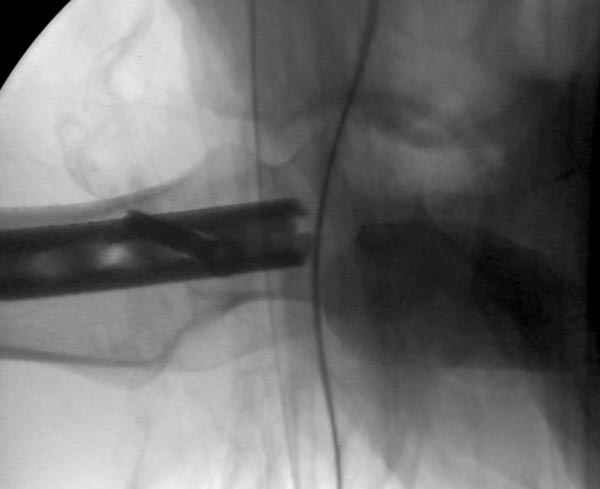

Второй случай тоже репозиция из малого доступа, больному 19 лет, множественные огнестрельные повреждениия конечностей, живота и черепа, правая конечность холодная, без пульсации. Ортопедический диагноз: огнестрельный перелом правого бедра. При срочной ангиографии повреждения сосудов не подтвердилось, конечность из-за ургентности состояния больного зафиксирована временным наружным фиксатором и больной оставлен на операционном столе для срочной лапаротомии хирургической службой.